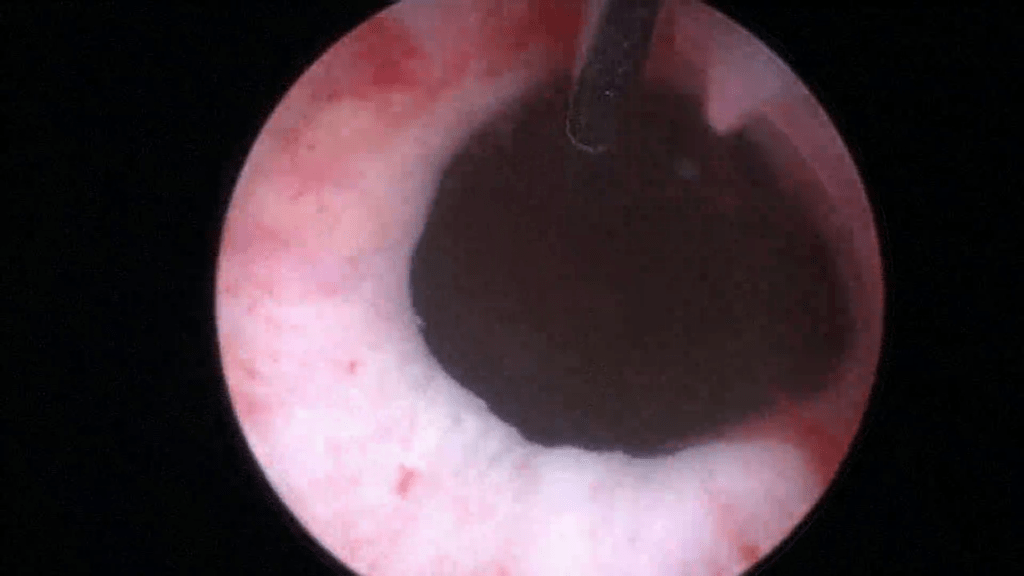

Start on the 12 o’clock position and gently press the cystoscope against the anterior urethral wall while making sure its axis remains parallel to the urethra. This will create a small “mucosal shelf”, in which the needle can vertically penetrate the urethra.

The bevel of the needle should be facing towards the center of the lumen.

Insert the needle up to the 1cm mark.

Begin injecting Bulkamid® hydrogel.

Image after injecting 0.5ml at the 12 o’clock position.